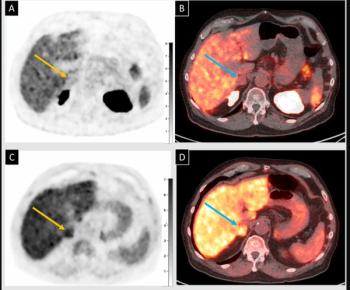

The dual-targeted 177Lu-DOTA-FAPI-RGD reportedly reduced or stopped the growth of cancer lesions in 88.9 percent of advanced adenocarcinomas in a small cohort of patients with varied cancers including pulmonary, pancreatic and ovarian cancer, according to new research presented at the SNMMI conference.